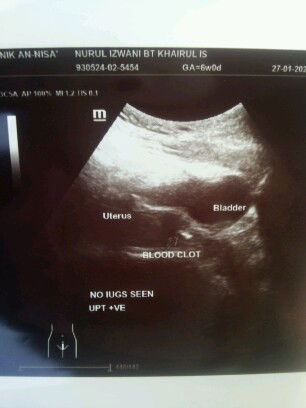

Salam..saya nak tanya sapa pernah first scan nampak kantung.. kali kedua scan ta nampak kantung just nampak ketui darah beku mcm ni.. doc kata scan nampak gini kemungkinan janin tak menjadi kantung mngecut..tapi doc refer saya ke pakar hospital utk double comfirm tapi hospital scan tak nampak pun ketui darah mcm gini cuma nampak baby kecik..spatutnya 6week tapi scan tak macam 6week..hospital bg masa 2week utk repeat scan tengok janin berkembang atau tak....saya 4tahun menanti ini kandungan ke5.. doc cakap byk2 berdoa maa tahu rezeki Allah bagi janin tu akan membesar ka..hospital xdpt bg jawapan lg.. agak2 ada chance tak baby ni berkembang..saya susah hati fikir..